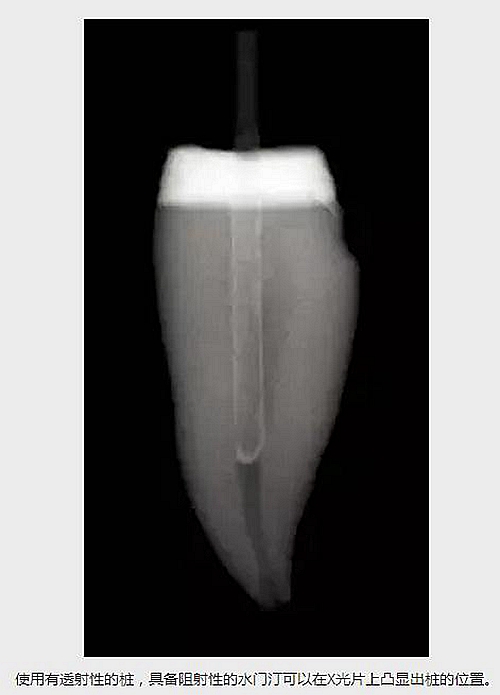

水門汀的阻射性,比如Multilink Automix (Ivoclar /Vivadent)或者使用其他水門汀。如果使用了一個(gè)有透射性的樁,有阻射性的水門汀可以在X光片上凸顯出樁的外形。 (見下圖)

使用有透射性的樁,具備阻射性的水門汀可以在X光片上凸顯出樁的位置。